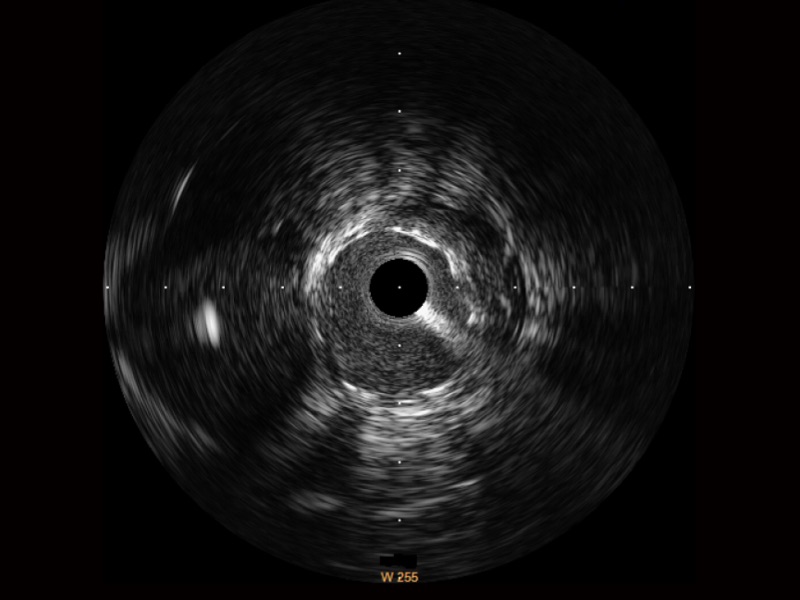

竞技宝(JJB)官方网站超宽频成像技术覆盖20-80MHz1或20-90MHz2频率范围, 提供优异的分辨力同时也保证充足的穿透深度

对比传统IVUS导管成像,竞技宝(JJB)官方网站宽频IVUS图像的近场支架梁显影更细腻,远场中膜外血管仍清晰可辨,兼顾远中近,兼顾分辨力与穿透深度